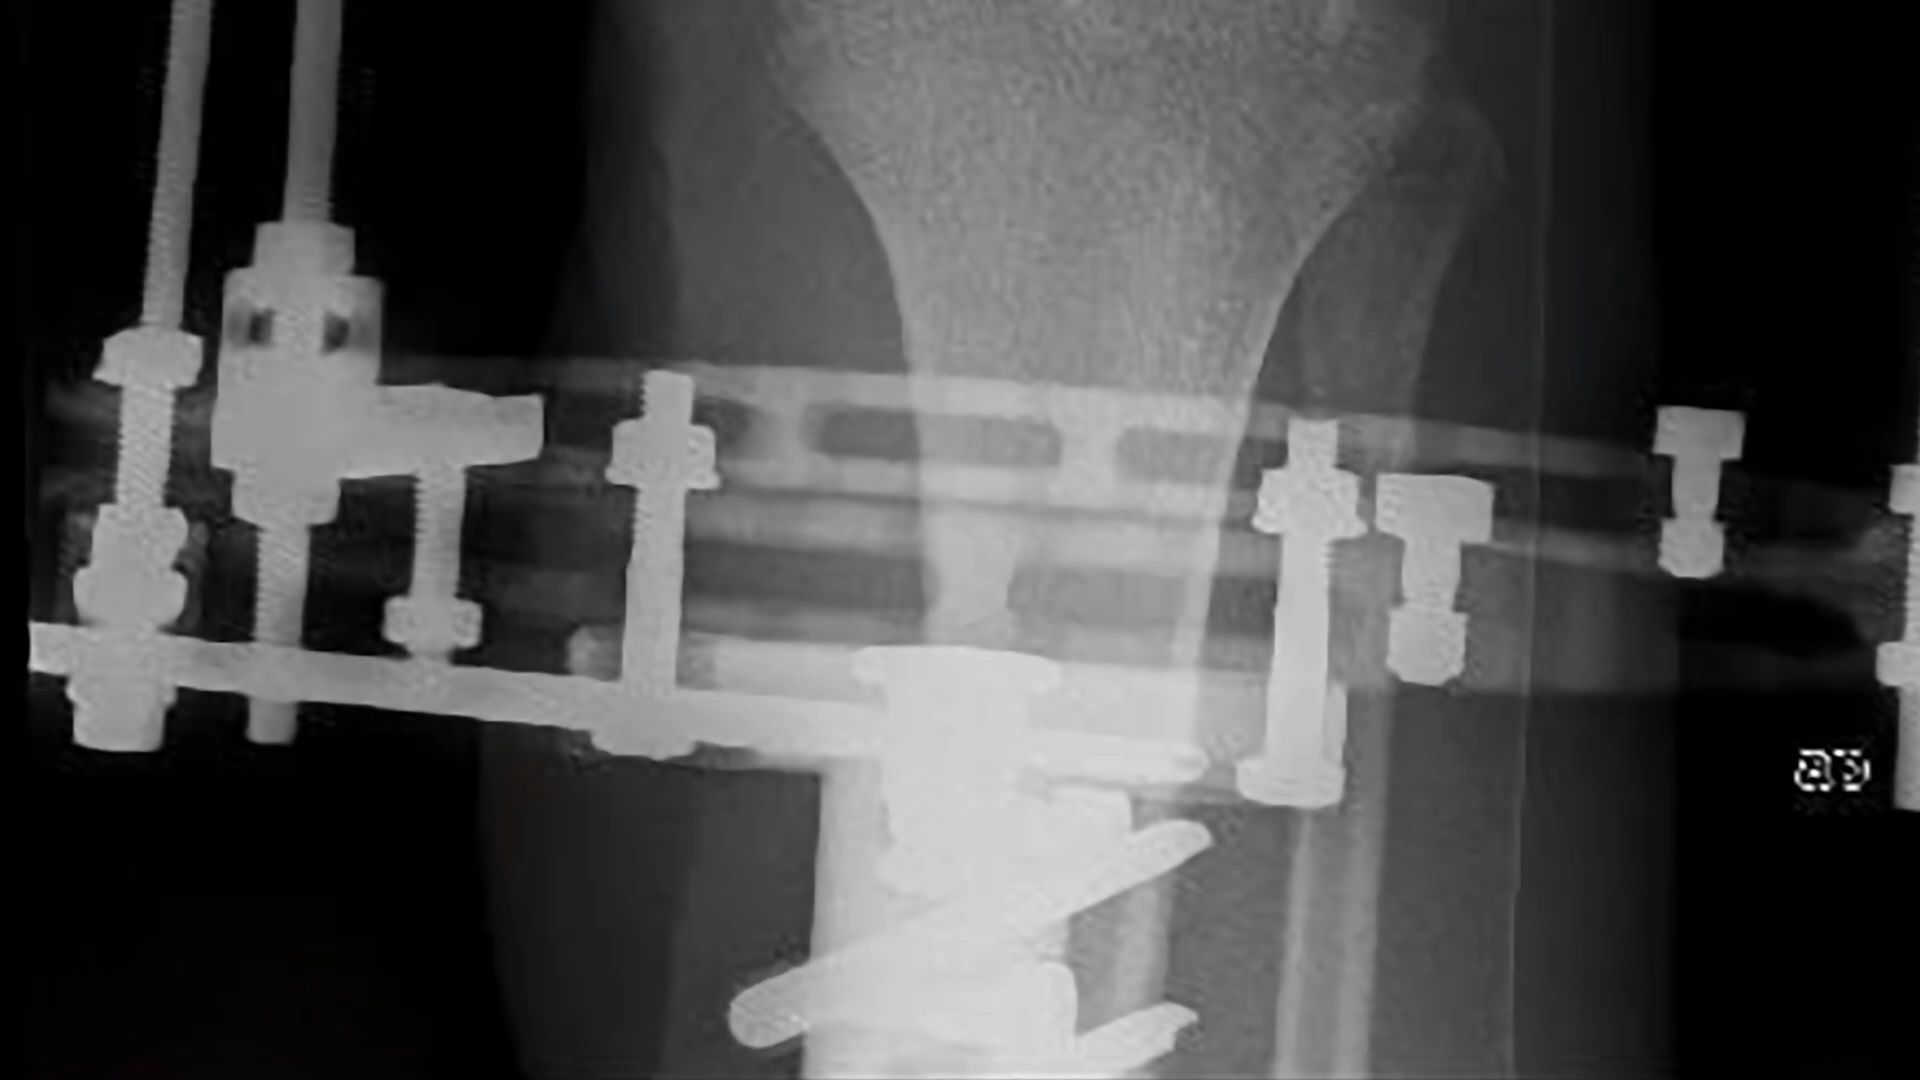

BAND-AID "WILL REYNOLDS"

Produced, Shot, Directed, & Edited this piece for Band-Aid brand, celebrating veteran's organization Team RWB and Invictus Games US team captain Will Reynolds .